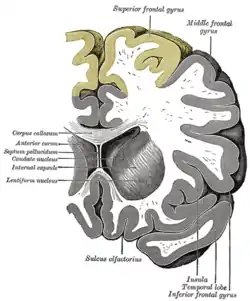

![]() Coronal section through anterior cornua of lateral ventricles. Superior frontal gyrus is shown as yellow. | |